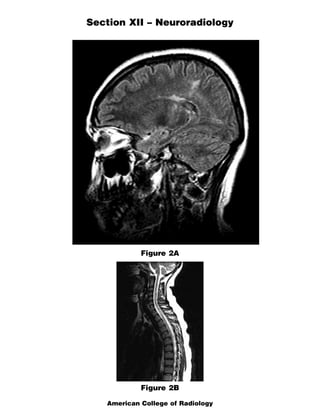

The document discusses several radiology cases involving the brain and spine. Question 291 presents CT scans of a woman with headaches and asks for the most likely diagnosis of a fat-containing extraconal orbital mass. Question 292 shows MR images of a woman with extremity weakness and asks for the most likely diagnosis of multiple brain and spine lesions. Question 293 presents MR images of a man with back pain and asks for the diagnosis of a posterior spinal mass seen on the images.